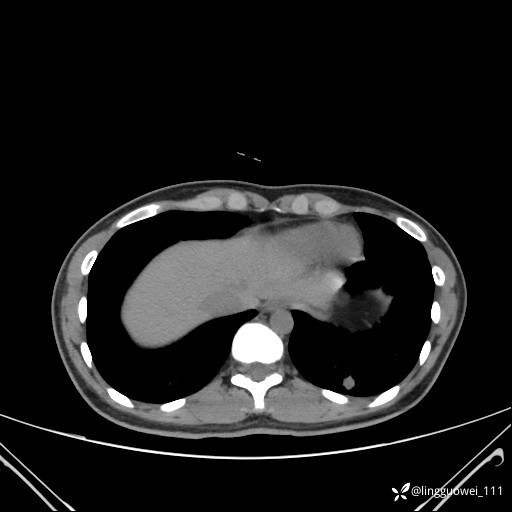

患者性别:女

患者年龄:26岁

主诉:咳嗽来诊,结节性质不明。

肺毛细血管瘤 (2)